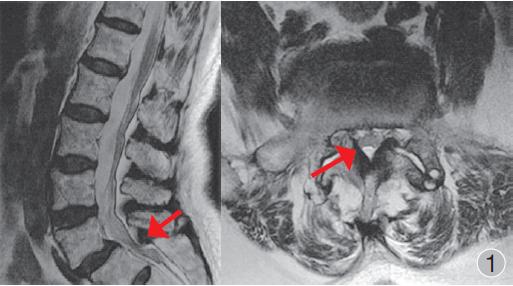

2、腰椎管狭窄有许多类型,比如合并脊柱侧弯、脊椎滑脱等。

3、退行性脊柱侧弯会出现向侧方弯曲的现象,这种畸形绝大多数发生在腰椎。

4、退行性脊椎滑脱是由于长期的椎间盘导致的椎间关节不稳定,表现为上位脊椎向前发生滑移。